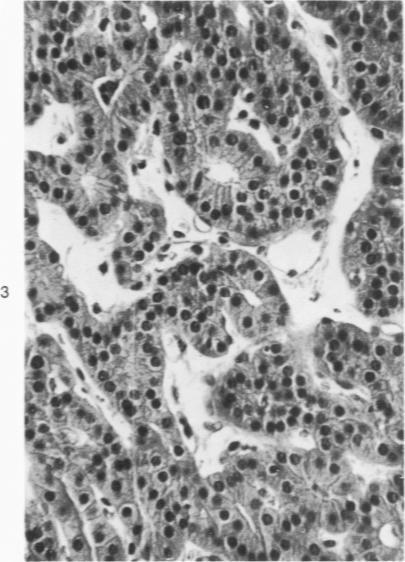

Oxyphil cells and oxyphil cell adenomas of parathyroid glands are, in most instances, regarded to be nonfunctioning. Although 21 cases of hyperparathyroidism associated with parathyroid oxyphil cell adenoma have been reported, secretion of hormone by these tumors has not been conclusively demonstrated. A parathyroid adenoma, diagnosed by light microscopy as oxyphil type, together with the results from ultrastructural and biochemical studies of the patient's adenomatous tissue, are reported here. The patient, a 64-year-old male, was found to have elevated serum calcium, low serum phosphorus, and elevated serum immunoreactive parathormone: findings consistent with hyperparathyroidism. After excision of two small normal-appearing glands and one greatly enlarged (1.9 g) parathyroid gland, those laboratory values returned to normal. Light microscopy of the enlarged parathyroid indicated that it consisted almost entirely of an oxyphil adenoma. Electron microscopy revealed that the adenoma was composed mainly of mitochondria-rich oxyphil cells but also of interspersed transitional oxyphil cells and rare scattered chief cells. Golgi zones, rough endoplasmic reticulum, and prosecretory and secretory-like granules were observed in some oxyphil cells, in most transitional oxyphil cells, and in the infrequent chief cells. Thus, many of these cells appear to contribute to the production and secretion of parathormone. Biochemical studies performed directly on the adenomatous tissue demonstrated that it was able to synthesize proparathormone and parathormone, although the proportion of hormonal peptide synthesis relative to that of the total protein synthesis in this tissue was much smaller (0.9%) than that found in normal parathyroid tissue (5.7%). There was a small increase in immunoreactive parathormone when the adenoma tissue was incubated in a low-calcium medium. These findings indicate that this oxyphil adenoma of the parathyroid gland synthesized and secreted parathormone, apparently to some extent autonomously, but suggest that its capacity to do so was largely dependent on its component of cells other than fully developed oxyphil cells, such as transitional oxyphil cells.